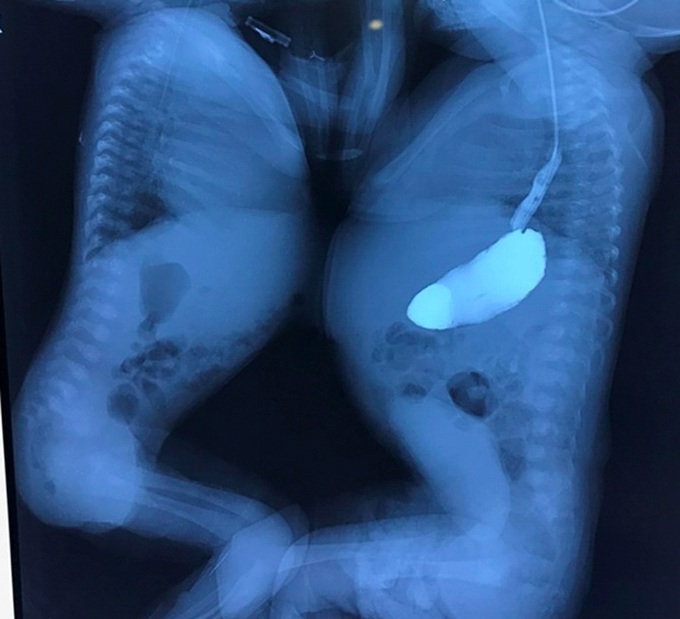

The two infants, V.N and V.T, were found to be conjoined twins when the mother was pregnant at 33 weeks. Local doctors performed a caesarean section seven weeks later, and the two babies were born weighing 2.2kg and 2.8kg respectively.

After careful examinations, the Hanoi-based doctors concluded that V.T is in stable health while V.N is in critical condition.

V.N suffered atrioventricular septal and single ventricle defects, severe atrioventricular valve regurgitation, aortic disruption, arterial inversion, and pulmonary atrophy.